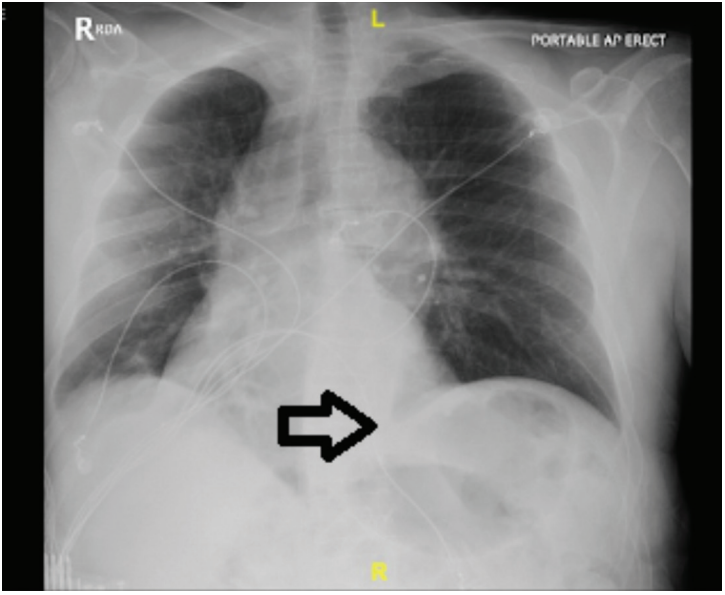

Due to symptoms consistent with unstable angina and a high pretest probability for CAD, a decision was made to take the patient to the cath lab the same day. Left heart catheterization was performed and showed patent coronaries. Prominent elevation of the left diaphragm was seen on multiple cine views with bowel visualization above the heart (Video). Transthoracic echo showed low normal ejection fraction but was otherwise unremarkable. Chest computed tomography (CT) angiography and chest x-ray were negative for pulmonary embolism and showed eventration of the left hemidiaphragm (Figures 1-3).